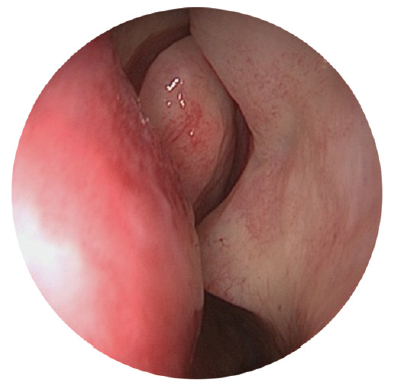

The study included patients with complaints of long-term lacrimation and suppuration (more than 6 months). The patients were diagnosed and treated at various institutions – at otorhinolaryngological and ophthalmological departments of the Pirogov State clinical hospital (Moscow) and hospitals of the MEDSI group of companies (Moscow) with the established diagnosis of “chronic dacryocystitis” during the period from 2015 to 2019. The clinical examination of patients included disease history, biomicroscopy of the anterior segment with evaluation of the eyelids, and anterior rhinoscopy. Endoscopic examination of the nasal cavity was performed using rigid endoscopes of 0° and 30° and 4 mm in diameter, after local application anesthesia with 10% lidocaine hydrochloride solution, with examination of all the endonasal structures of the nasal cavity: inferior nasal meatus, nasal floor, inferior nasal concha, middle nasal meatus, osteomeatal complex, area of the hamate bone, front end of the middle turbinate, and lacrimal tubercle of the nasal septum (Fig. 1–3).

Fig. 1. Endoscopy of the nasal cavity. Endoscope 4 mm 0°. The lacrimal tubercle covers the area of projection of the lacrimal sac